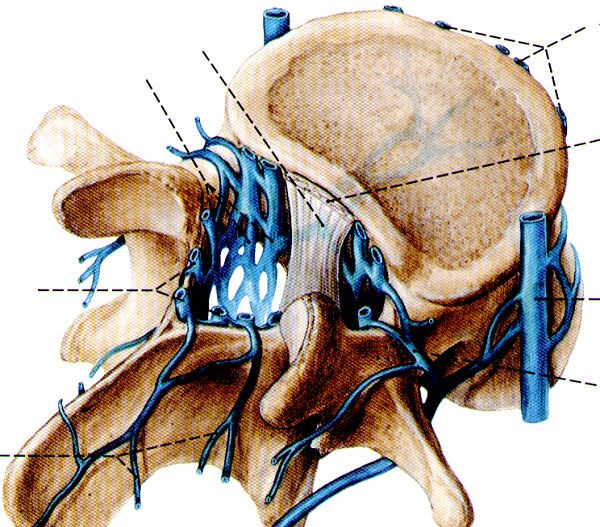

一、椎管的应用解剖

前壁:椎体、纤维环、后纵韧带。

后壁:椎弓和黄韧带。

两侧:椎弓根、上下关节突及关节囊,并以椎间孔向外开放。

黄韧带:起于上位椎管的下前缘,止于下位椎管的上后缘。

中央椎管:各腰椎椎孔形状,腰1、2多呈卵圆形,腰3、4多呈三角形,腰5多呈三叶形,其他尚可呈钟形、或橄榄形。因退变或其他病变、椎孔形状还可有不同改变。腰椎椎管自腰1、2间隙以下包含马尾神根.其被硬脊膜包围的部分形成硬膜囊,各种经根自硬膜囊发出后在椎管内的一段称为神经根管,以后分别自相应椎间孔穿出。

腰神经通道:腰神经根自硬脊膜囊发出后,经过较窄的骨纤维性管道,由椎间管穿出的径路统称为腰神经通道。此通道分为两段,第一段为神经根管,从硬膜囊穿出点至椎间管内口,第2段为椎间管

盘黄间隙:即椎间盘与黄韧带之间的间隙。

侧隐窝:侧隐窝位于侧椎管,也是神经根管的狭窄部分。